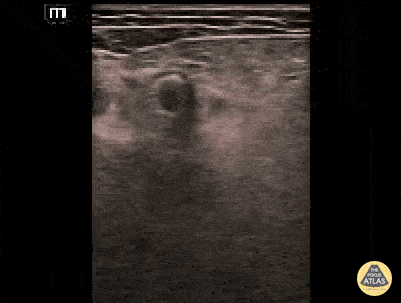

Femoral artery stent can be appreciated in this short axis view as a bright, hyperechoic structure within the femoral artery borders. Contributed by: Brittany Garza, DO; Saleem Nasseh, MD; Sadie Ellerson, MS4